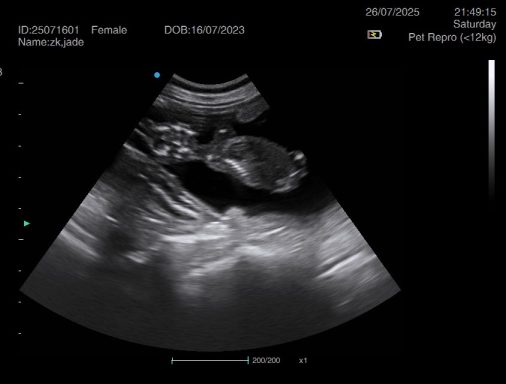

Ultrasound pregnancy scanning is a safe, non-invasive way to confirm pregnancy in dogs and cats, offering breeders and pet owners peace of mind and vital information to support responsible care. It allows us to detect gestational sacs, assess foetal development, and estimate litter size—all while ensuring the wellbeing of the animal.

Pregnancy can sometimes be detected as early as Day 18 post-mating, but scanning at this stage is not routinely recommended. Embryos are still developing and may not be clearly visible, and there is a natural risk of embryo resorption, which can lead to misleading or inconclusive results.

For the most accurate and reliable scan, we advise booking between Day 25 and Day 32, when pregnancy is more easily confirmed and foetal structures are clearer. If an early scan is performed and no pregnancy is detected, we offer a FREE complimentary re-scan after 7 days at the clinic to ensure clarity and support informed decision-making.

Our approach balances early insight with ethical care—always prioritizing the comfort of the animal and the accuracy of the results.